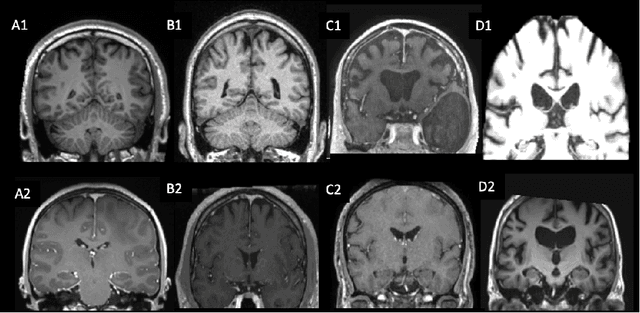

Abstract:The emergence of clinical data warehouses (CDWs), which contain the medical data of millions of patients, has paved the way for vast data sharing for research. The quality of MRIs gathered in CDWs differs greatly from what is observed in research settings and reflects a certain clinical reality. Consequently, a significant proportion of these images turns out to be unusable due to their poor quality. Given the massive volume of MRIs contained in CDWs, the manual rating of image quality is impossible. Thus, it is necessary to develop an automated solution capable of effectively identifying corrupted images in CDWs. This study presents an innovative transfer learning method for automated quality control of 3D gradient echo T1-weighted brain MRIs within a CDW, leveraging artefact simulation. We first intentionally corrupt images from research datasets by inducing poorer contrast, adding noise and introducing motion artefacts. Subsequently, three artefact-specific models are pre-trained using these corrupted images to detect distinct types of artefacts. Finally, the models are generalised to routine clinical data through a transfer learning technique, utilising 3660 manually annotated images. The overall image quality is inferred from the results of the three models, each designed to detect a specific type of artefact. Our method was validated on an independent test set of 385 3D gradient echo T1-weighted MRIs. Our proposed approach achieved excellent results for the detection of bad quality MRIs, with a balanced accuracy of over 87%, surpassing our previous approach by 3.5 percent points. Additionally, we achieved a satisfactory balanced accuracy of 79% for the detection of moderate quality MRIs, outperforming our previous performance by 5 percent points. Our framework provides a valuable tool for exploiting the potential of MRIs in CDWs.

Abstract:Many studies on machine learning (ML) for computer-aided diagnosis have so far been mostly restricted to high-quality research data. Clinical data warehouses, gathering routine examinations from hospitals, offer great promises for training and validation of ML models in a realistic setting. However, the use of such clinical data warehouses requires quality control (QC) tools. Visual QC by experts is time-consuming and does not scale to large datasets. In this paper, we propose a convolutional neural network (CNN) for the automatic QC of 3D T1-weighted brain MRI for a large heterogeneous clinical data warehouse. To that purpose, we used the data warehouse of the hospitals of the Greater Paris area (Assistance Publique-H\^opitaux de Paris [AP-HP]). Specifically, the objectives were: 1) to identify images which are not proper T1-weighted brain MRIs; 2) to identify acquisitions for which gadolinium was injected; 3) to rate the overall image quality. We used 5000 images for training and validation and a separate set of 500 images for testing. In order to train/validate the CNN, the data were annotated by two trained raters according to a visual QC protocol that we specifically designed for application in the setting of a data warehouse. For objectives 1 and 2, our approach achieved excellent accuracy (balanced accuracy and F1-score \textgreater 90\%), similar to the human raters. For objective 3, the performance was good but substantially lower than that of human raters. Nevertheless, the automatic approach accurately identified (balanced accuracy and F1-score \textgreater 80\%) low quality images, which would typically need to be excluded. Overall, our approach shall be useful for exploiting hospital data warehouses in medical image computing.